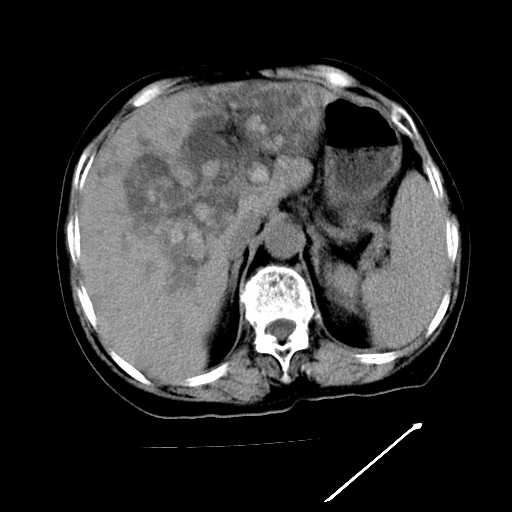

以下是引用随光逐影在2009-4-7 8:21:00的发言:[br]肝内外胆管多发性结石并肝内外胆管扩张;胆系感染。